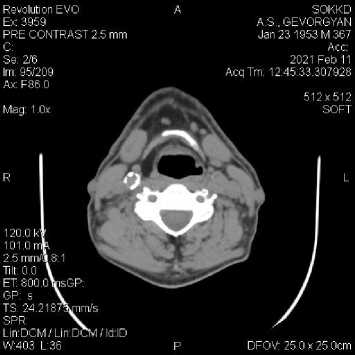

В ноябре 2020 года у пациента М., 68 лет с симптомами недомогания, выраженной общей слабости, повышения температуры тела до фебрильных значений и болью в горле в поликлинике по месту жительства при проведении ПЦР было подтверждено наличие новой коронавирусной инфекции COVID-19. Выполнена компьютерная томография (КТ) органов грудной полости, по результатам которой определены зоны уплотнения лёгочной ткани по типу «матового стекла» с объёмом поражения до 38%. Согласно рекомендациям участкового терапевта, произведён МСКТ-контроль органов грудной клетки в Самарском областном клиническом кардиологическом диспансере (СОККД) им В.П. Полякова спустя месяц от начала заболевания: отмечается положительная динамика в виде остаточных явлений перенесённой двусторонней вирусной пневмонии, также обращает на себя внимание выраженный кальциноз коронарных артерий.

Из анамнеза заболевания: последние пять лет отмечает повышение артериального давления (АД) максимально до 200 и 110 мм рт. ст., принимал гипотензивную терапию ситуационно (каптоприл). На фоне гипертонического криза отмечал эпизоды головокружения, шума в ушах, мелькание «мушек» в глазах. Ранее не обследовался.